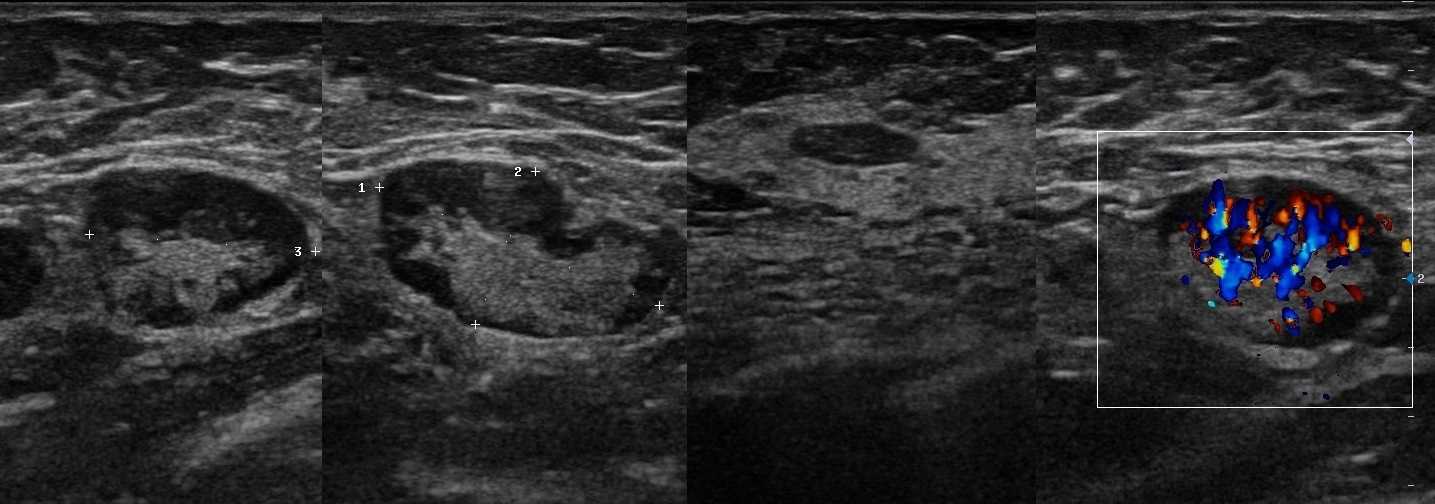

Злокачественная опухоль, первым признаком которой, является увеличение подчелюстных, шейных и надключичных ЛУ, при полном отсутствии заболеваний этой зоны. На эхограмме определяется группа узлов, преимущественно округлой формы, с хорошо определяемой капсулой, однородной гипоэхогенной структурой. Все узлы, собраны в «пачку», но в отличие от лимфоидной ткани, подвергшейся метастатическому поражению, не сливаются между собой и сохраняют целостность капсулы.

На УЗ-снимке: изображение той же лимфомы, выполненное в режиме ЦДК. В структуре лимфоузла прослеживается сосудистый рисунок